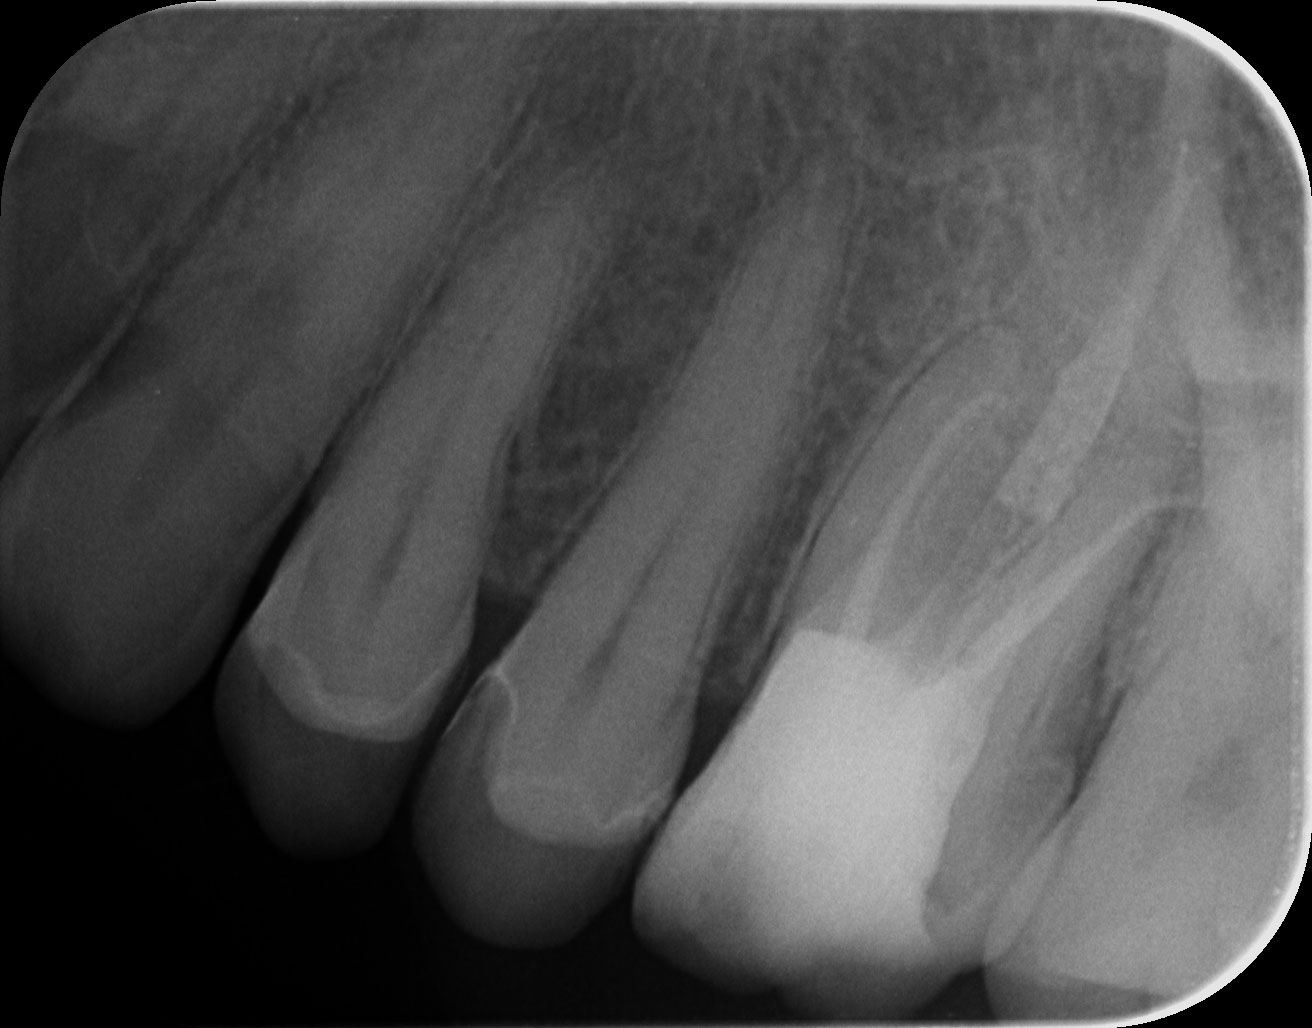

Dantų kanalų gydymas